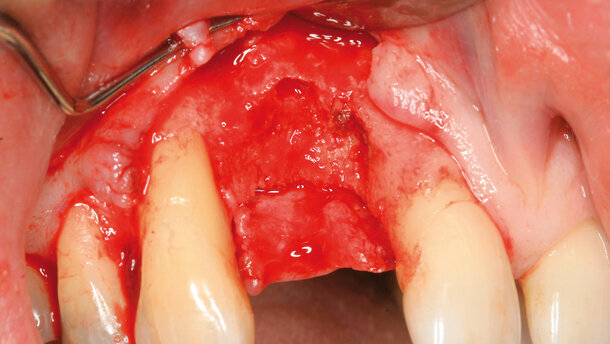

Figs. 2 & 3_Dégradation parodontale avancée au niveau de l’incisive latérale supérieure droite. La lésion intra-osseuse concerne la corticale vestibulaire de l’os. La dent voisine présente également une lésion parodontale intra-osseuse.

Fig. 4_Situation clinique immédiatement après l’extraction dentaire.

Un patient âgé de 51 ans, atteint d’une parodontite généralisée nous avait été adressé pour un traitement parodontal complet. Une lésion parodontale avancée a été observée au niveau de l’incisive latérale supérieure droite, dont la mobilité était de niveau III (voir la radiographie standard, Figs. 1a et b). Des poches parodontales de profondeur importante ont été détectées autour des dents voisines. Après l’élévation d’un lambeau, une lésion cratériforme à deux parois a été constatée sur la face mésiale de la dent, parallèlement à une absence de corticale vestibulaire (Figs. 2 et 3). L’extraction dentaire a été suivie par les procédures graduelles décrites précédemment (Figs. 4–7). Avec la première chirurgie, une augmentation des tissus mous a permis d’obtenir une morphologie de la crête alvéolaire autorisant la pose d’un implant avec nouvelle augmentation osseuse simultanée (Figs. 8–12). Pendant la liaison du pilier implantaire, on a pu constater une reconstruction tridimensionnelle de la crête alvéolaire autour de l’implant précédemment placé en position supracrestale. Cette approche chirurgicale a permis d’obtenir un nouvel accès aux lésions parodontales adjacentes, qui révélaient un comblement osseux et une complète régénération des lésions à une paroi antérieure. Après la cicatrisation des tissus mous, une couronne temporaire a été vissée in situ, afin d’assurer la formation d’un profil d’émergence idéal pendant encore trois mois. Cette situation a ensuite été transférée sur le modèle, pour élaborer la couronne céramo-métallique permanente. Voir la figure 14 pour la restauration définitive.